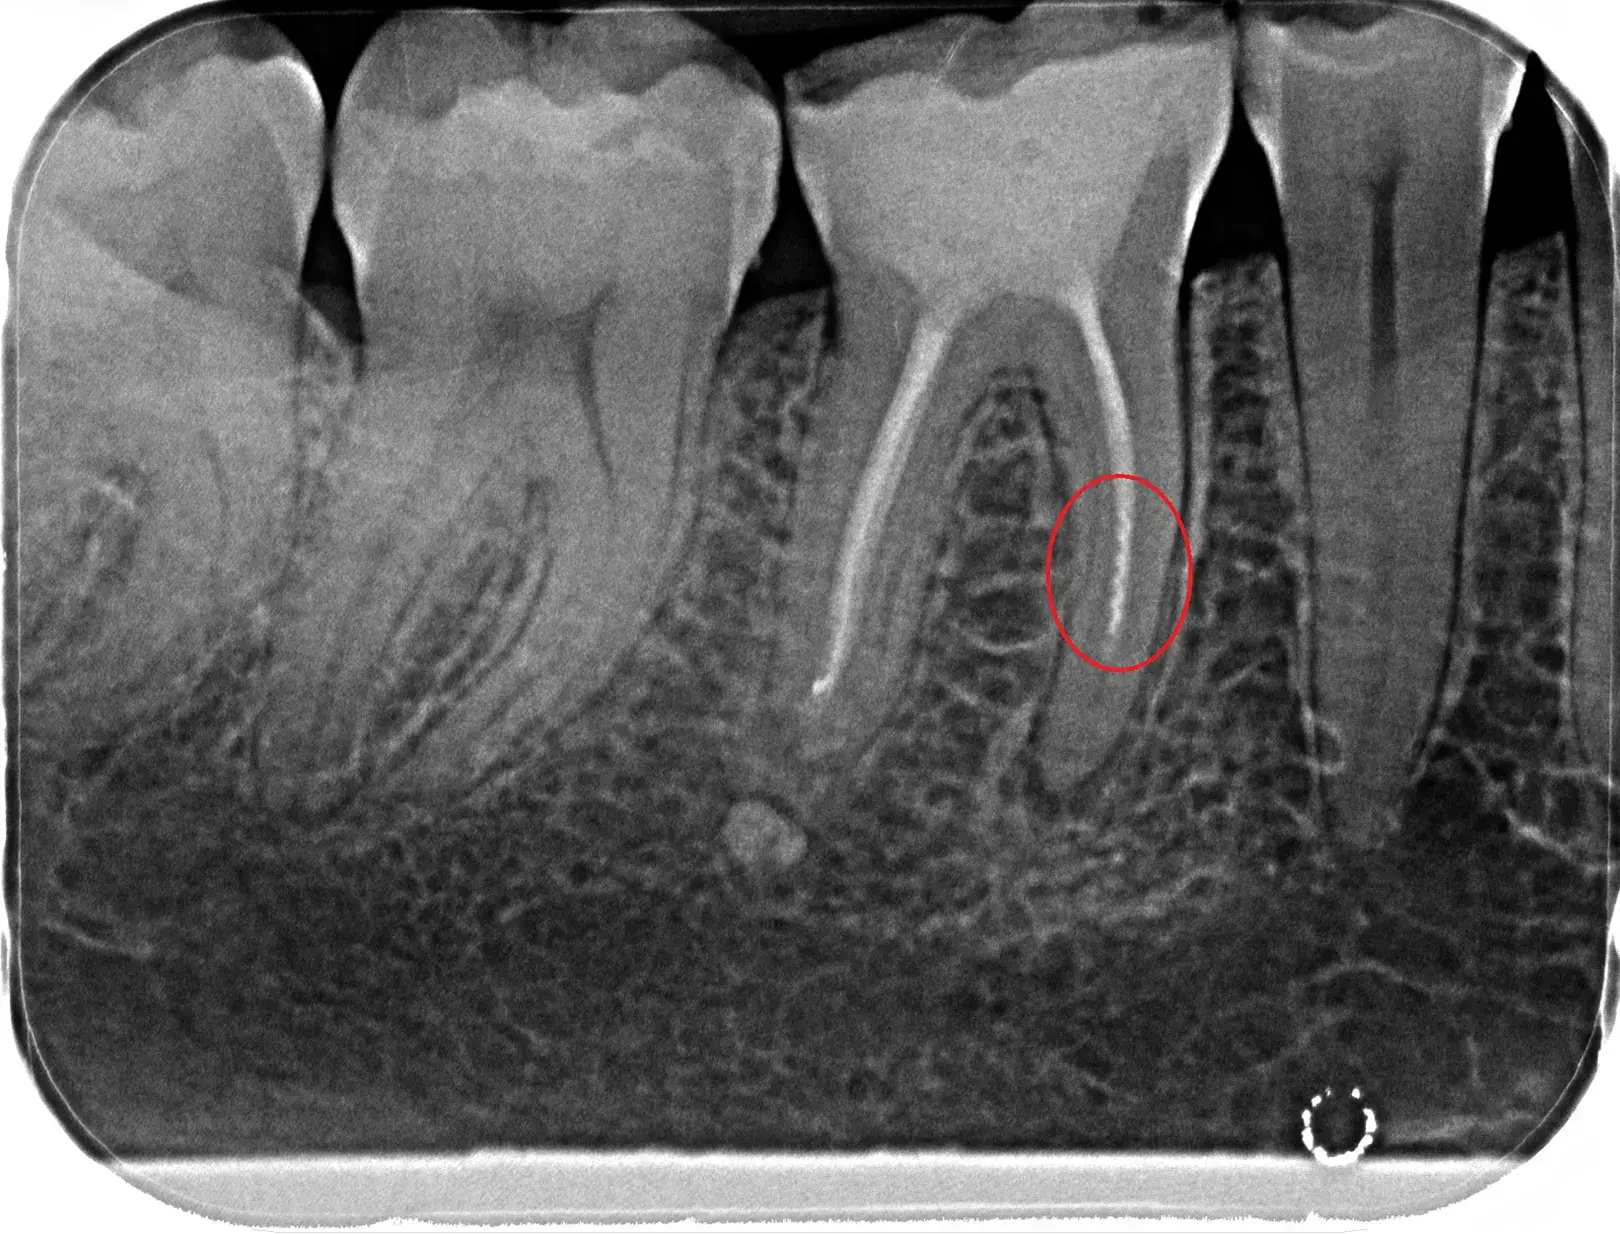

In der modernen Zahnmedizin entscheiden oft Millimeter über den langfristigen Erhalt eines Zahnes. Während eine herkömmliche Lupenbrille in vielen Fällen ausreicht, stoßen wir bei komplexen Wurzelbehandlungen (Endodontologie) manchmal an anatomische Grenzen, die das bloße Auge nicht mehr erfassen kann.

Ein aktuelles Beispiel aus unserer Praxis (siehe Bild) zeigt einen Backenzahn mit fünf statt der üblichen drei Wurzelkanäle. Solche feinen Verästelungen sind eine absolute Rarität und ohne entsprechende Technik kaum zu lokalisieren.